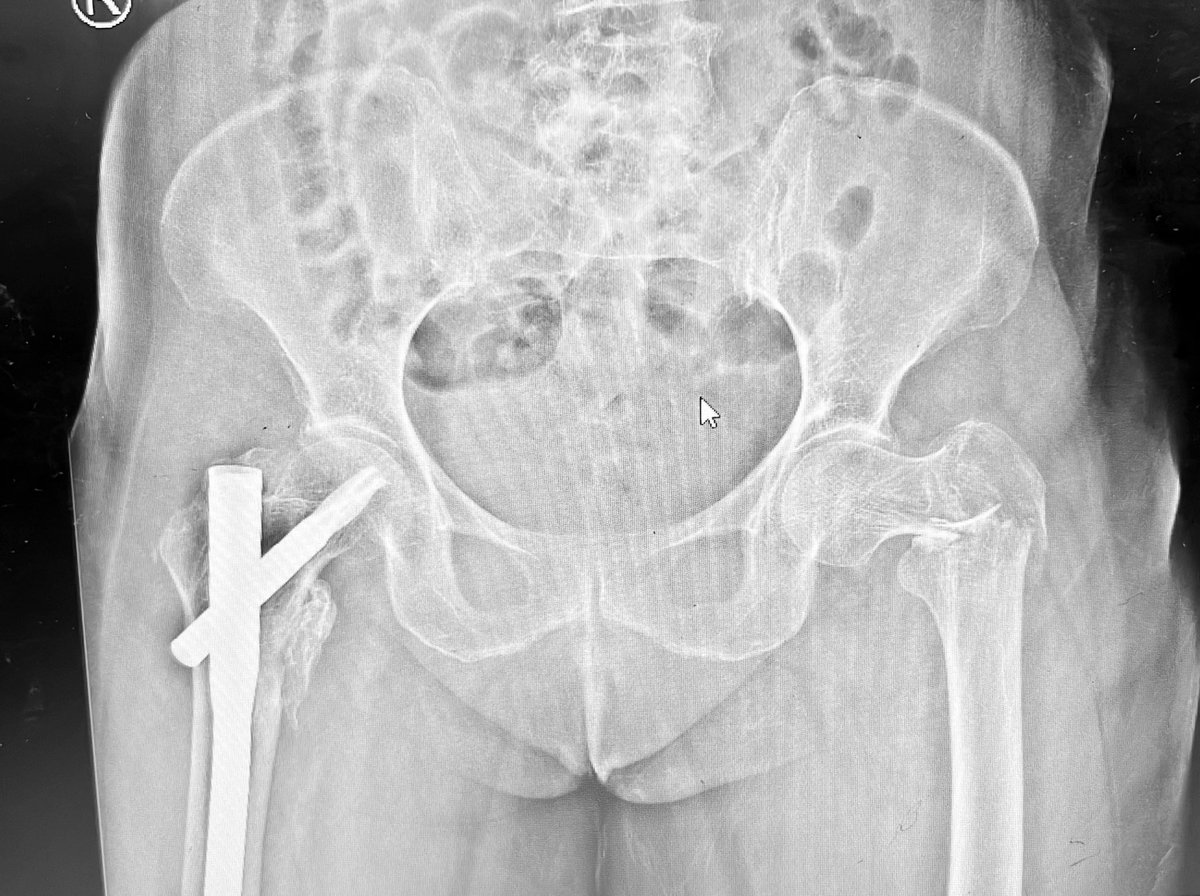

77 yo, pluripathological patient, combo nail and plate. Suprapatellar nail

Dr. Diego López tweet mediaDr. Diego López tweet mediaDr. Diego López tweet media